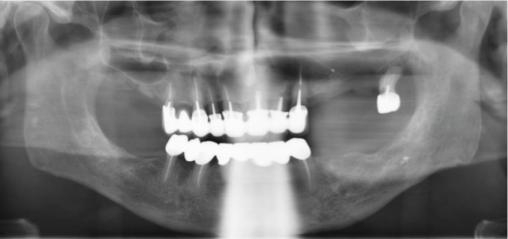

Le panoramique dentaire (fig. 1) met en évidence une solution de continuité de l’os alvéolaire au niveau de la dent 26 extraite. L’aspect est bourgeonnant (fig. 2). Un prélèvement histologique est effectué, qui montre une métaplasie malpighienne avec dysplasie de haut grade, sans infiltration du chorion, au niveau de la zone de jonction entre l’épithélium malpighien de surface et l’épithélium cylindrique cilié sinusien.

Le bilan d’extension étant négatif, la prise en charge a consisté en une maxillectomie partielle avec avulsion de la dent 27 (fig. 3).